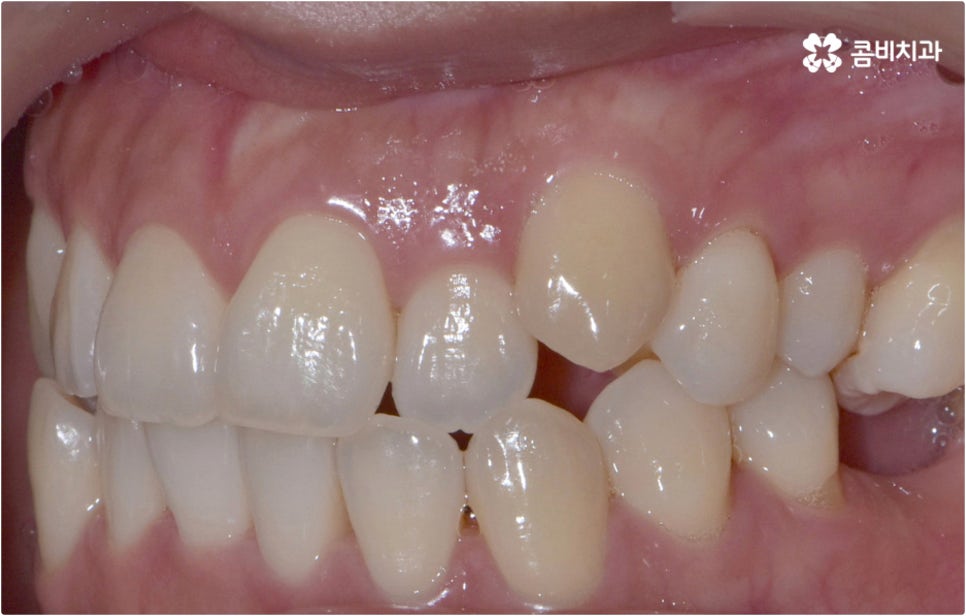

치아설측교정 은 겉으로 장치가 드러나지 않아서 가까운 사람이 아니면 교정 치료를 진행한다는 것을 알아차리기 힘들 정도로 심미성이 뛰어난데, 이러한 장점을 가지고 있는 반면 혀가 아랫니 쪽 장치에 닿다 보니 발음이 불분명해지거나 이물감 및 통증을 느끼는 경우가 있어 주의할 필요가 있어요.

이런 때는 치아설측교정 대신 비교적 잘 보이는 윗니는 설측으로 진행하고, 입술에 가려 잘 보이지 않는 아랫니는 순측(입술쪽)으로 진행하는 콤비교정을 이용하면 발음, 이물감, 통증 문제를 해결할 수 있습니다. 콤비교정 시 치아 겉면에 부착하는 아랫니 브라켓의 경우 치아와 색상이 비슷한 세라믹 재질을 이용하기 때문에 심미성도 크게 떨어지지 않으며 치아설측교정 으로 전체를 진행하는 것 보다 비용적인 부담도 줄여주므로 설측 교정 치료를 생각하시는 분들이라면 콤비교정 역시 함께 알아보시길 권유드리고 있어요.

이와 같이 치아설측교정 과 콤비교정은 브라켓을 치아 안쪽으로 붙여서 치료하는 방식이기 때문에 굉장히 고난도의 복잡한 교정 치료라고 할 수 있습니다. 교정에 대한 높은 이해도와 해부학적으로 뛰어난 노하우, 풍부한 경험을 통해 축적한 세심한 기술력을 갖추고 있는 의료진에게 치료를 맡기는 것이 중요하며 정밀 디지털 검진 장비를 통한 정확한 검사 결과를 바탕으로 무리하지 않게 진행하실 필요가 있어요. 또한 양치질을 할 때 음식물 제거가 쉽지 않으므로 환자분들 본인이 평상시 신경써서 닦아주시는 것은 물론 꼼꼼한 케어시스템을 통해 주기적으로 관리해 주는 치과에서 교정 치료 및 사후 유지 관리까지 철저하게 받아보시길 권유드리고 있습니다.